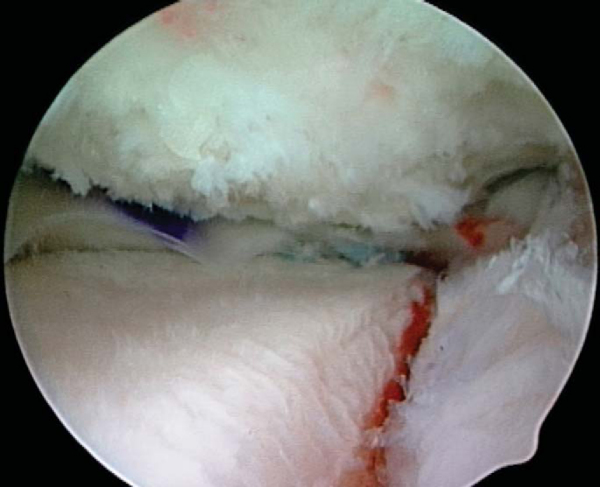

5. Meniscus Insertion and Fixation

). With the aid of the traction sutures, the meniscal allograft is pulled into the joint through the anterior arthrotomy while the bone bridge is advanced into the tibial slot, and the meniscus is manually reduced under the condyle with a finger placed through the arthrotomy (

Fig. 47-14

). Appropriate valgus or varus stress to open the ipsilateral compartment aids in graft introduction and reduction. Once the meniscus is reduced, the knee is cycled to ensure proper placement and capturing by the tibiofemoral articulation, and the bone bridge is secured within the tibial slot with a bioabsorbable cortical interference screw. Finally, the graft is attached to the capsule with standard inside-out vertical mattress sutures placed equally on the dorsal and ventral meniscal surfaces (

Fig. 47-15

). This fixation can be supplemented with appropriate all-inside fixation devices placed most posteriorly and outside-in suture placed most anteriorly.